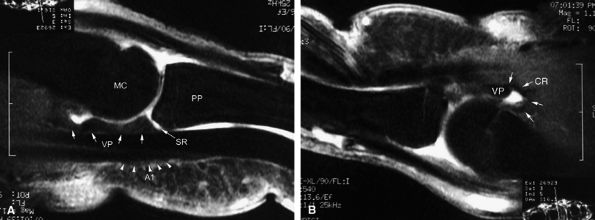

FIGURE 11.3 ● The volar plate of the metacarpophalangeal joint. (A) Midline and (B) parasagittal post-enhancement fat-suppressed sagittal T1-weighted images. VP, volar plate; SR, synovial recess; MC, metacarpal; PP, proximal phalanx; A1, A1 annular pulley; CR, checkrein.

|